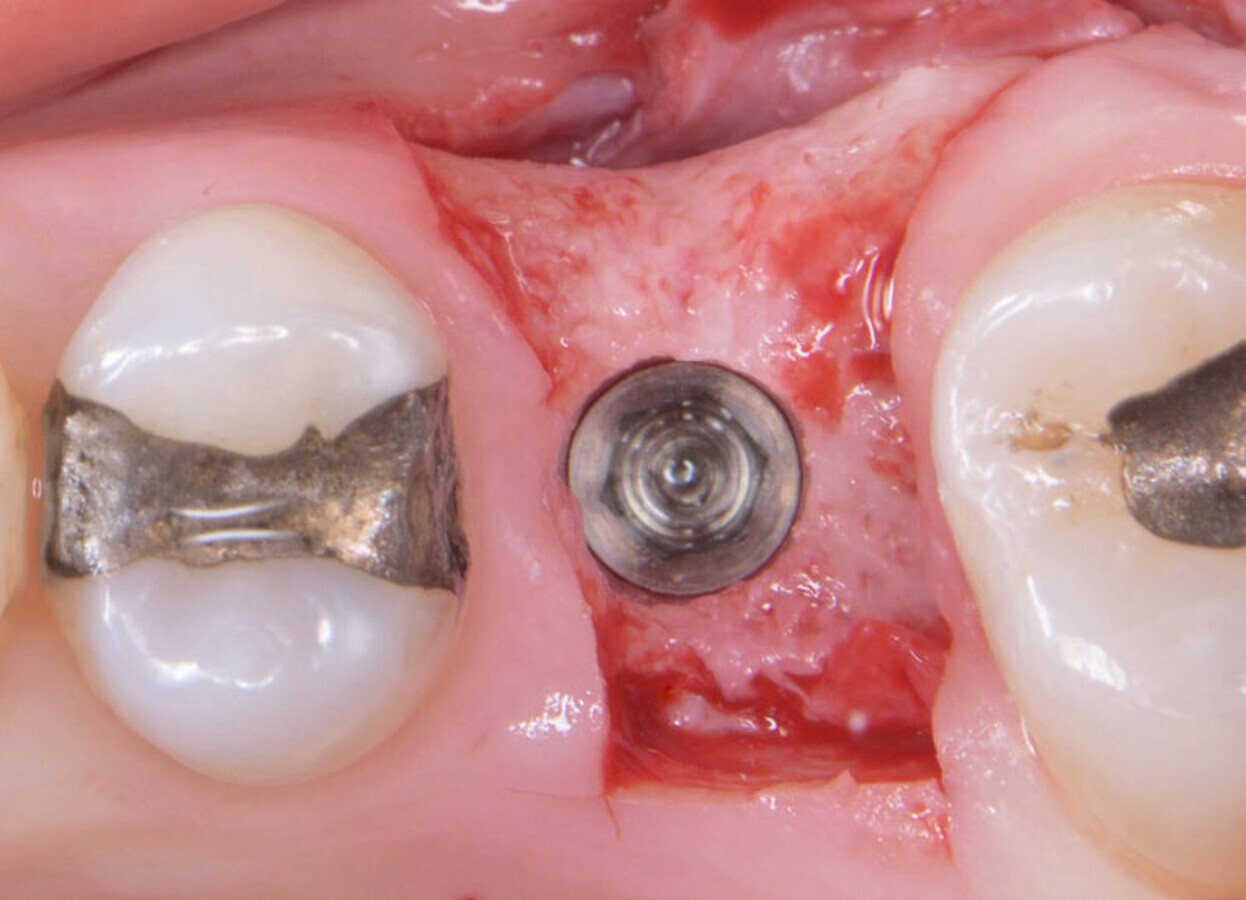

Implant in place with the driver.

No implant threads exposed.

EthOss grafting in fully guided implant placement case with Paltop Guided Implant System. Female 51-year-old patient, non-smoker, non-contributory medical history. Extraction of fractured and infected 26 carried out 10 months ago. Digital planning showed possible buccal defect, so flap raised and grafting was necessary. As expected the buccal bone defect shown on the CBCT was not an actual dehiscence defect, just thin immature bone. In any case the buccal concavity was grafted as usual with EthOss. Very precise, quick and minimally invasive procedure.